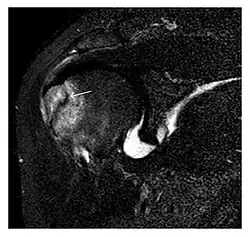

The greater tuberosity of the humerus is also an illustrative location of occult fractures. The osseous injury may follow seizures, glenohumeral dislocation, forced abduction, or direct impaction. They are commonly discovered on MRI in symptomatic patients with suspicion of rotator cuff tear. Coronal images are best suited for detection. They appear as crescentic oblique lines surrounded by a bone marrow edema pattern (Figure 5). The rotator cuff must be inspected since associated ligamentous lesions are common. In the ankle, malleoli and tarsal bones should be checked carefully for any cortical disruptions and radiolucent lines that may reveal a fracture. Awareness of the exact location of the pain will help direct the attention of the interpreter when searching for very subtle signs of fracture (Figure 6).[1]

-

a -

b

Figure 6: Subtle anterior talar fracture in a 39-year-old man presenting with ankle pain after a fall. (a) Anteroposterior radiograph shows a subtle oblique radiolucent line through the talus (white arrows). (b) Sagittal CT reformation confirms the presence of an anterior talar fracture with cortical offset (black arrow). Avulsion fractures, which consist of a detached bone fragment resulting from a ligament or tendon pulling away from the bone, may also present with subtle radiographic signs. Tiny osseous fragments near the presumed attachment site of a ligament suggest this diagnosis. Common sites are the lateral tibial plateau (the Segond fracture), the spinal tuberosity of the tibia resulting from anterior cruciate ligament avulsion, and the ischial tuberosity.[1]